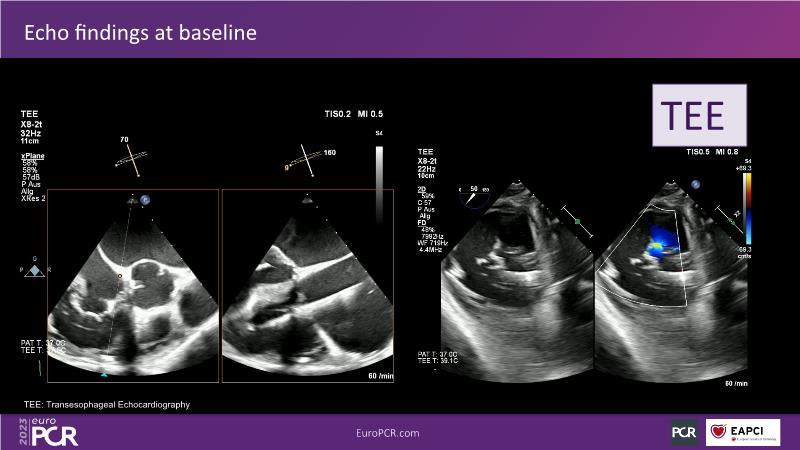

Tailoring tricuspid regurgitation patient treatment with the PASCAL Precision system

- To discuss the different tricuspid regurgitation phenotypes that can be treated with the PASCAL Precision repair system

- To participate in a case-based discussion using the PASCAL Precision repair system for the treatment of tricuspid regurgitation